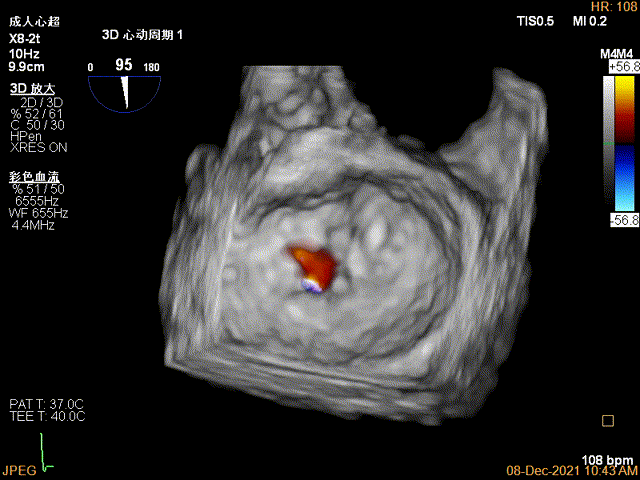

夹子关闭过程中,Color提示2区反流逐渐减少,残余反流位于夹子外侧

3D-Color-view验证残余分流位于外侧

1、此患者打破了风湿性心脏瓣膜患者不能做TEER治疗的传统观念,在经胸超声心动图的报告上风湿性心脏瓣膜病,二尖瓣瓣叶增厚,瓣口狭窄的初步印象让这个虚弱的患者险些错失了经导管介入治疗的机会。因此,对于每一个二尖瓣反流的患者,对其发病机制和解剖结构都需要全面细致的评估,即使是风湿性心脏瓣膜病变,也并非TEER治疗的绝对禁忌,利用经食道超声心动图的最新优势,结合2D、3D、 multivue、血流多普勒参数等多个维度去精准评估患者的解剖特征和血流动力学状态,为TEER治疗的可行性和手术测略做出准确判断。